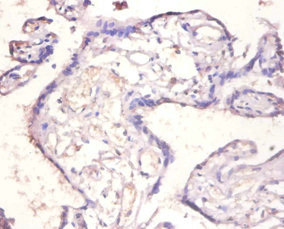

Immunohistochemistry of paraffin-embedded human placenta tissue using CSB-PA16739A0Rb at dilution of 1:100